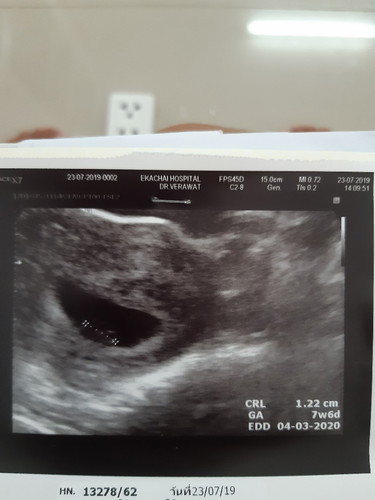

พอดีไปซาวอาทิตที่ผ่านมาอายุครรถ์ได้ 7 w6d แต่คุณหมอบอกว่าเด็กตัวเล็ก ฟังเสียงหัวใจก็ยังไม่ชัดเจน หมอนัดอีกที วันที่ 6 สิงหาตอนนี้กังวลมากค่ะ

ภาพนี้ตอนน้อง 6 week จ้า เห็นแค่ตัวอ่อนของน้อง หมอบอกเสียงหัวใจยังไมาต้องฟังค่ะเพราะน่องยังเล็กยุ หมอนัดอีกที ตอน7weekปลายๆเห็นหัวใจกระพริบแต่หมอยังไม่ให้ฟังเสียงมาฟังจริงๆตอน 10weekชัดแจ๋วจ้าแม่☺️ (ปัจจุบันน้อง15week4dจ้า)